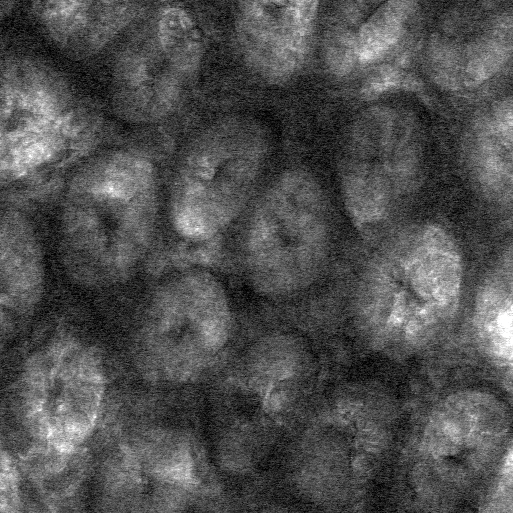

Our intestinal tracts are lined with a mucus gel that acts as a protective barrier between the insides of our bodies and the outside world. The gel lets in nutrients and largely blocks out bacteria, preventing infections. It also regulates how some drugs are delivered elsewhere in our bodies.

Researchers had previously studied how the gel can be damaged, for instance when bacteria feed on the gut's lining. The Caltech study is the first to look at the structure of the gel and how it morphs in the presence of other substances naturally found in the gut.

Performing their experiments in mice, the team tested the effects of polymers, which include dietary fiber as well as therapeutics such as medicines for constipation. The researchers fed some mice a diet rich in polymers and others (the controls) a polymer-free diet. Using a technique called confocal reflectance microscopy they measured the thickness of the gut gel and the degree to which the gel was compressed as a result of the consumed polymers. Mice given a high-polymer diet, they found, had a more compressed gel layer.

"The gel is like a sponge with holes that let material through," says the paper's lead author, Sujit Datta, a postdoctoral scholar in the laboratory of Rustem Ismagilov, Ethel Wilson Bowles and Robert Bowles Professor of Chemistry and Chemical Engineering. "We are seeing that polymers, including dietary fiber, can compress the gel, potentially making the holes smaller, and we think that this might offer protective benefits," Datta adds.

The researchers also found that dietary fiber and gut bacteria—which are part of a community of microorganisms collectively known as gut microbiota—can work together to influence how the gut gel changes shape. They performed the same polymer/fiber experiments in germ-free mice, which are mice carefully raised to not have any bacteria in their gut. The results showed that the polymers compressed the gut gels of these germ-free mice to a greater degree. This implies that species of bacteria in our gut that are known to break down polymers can weaken the compressing effect.

"We previously thought of the gel as a static structure, so it was unexpected to find an interplay between diet and gut microbiota that rapidly and dynamically changes the biological structures that protect a host," says Ismagilov.